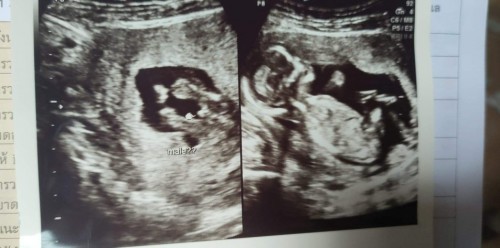

ของเรา12วีค ลักษณะแบบนี้เลยคะ หมอบอกเหมือนจะผู้ชาย ยังไม่คอนเฟิร์มพอเดือนที่4-5ไปใหม่ ชัดเจนคะ อะจู๋เต็มๆ😄😄